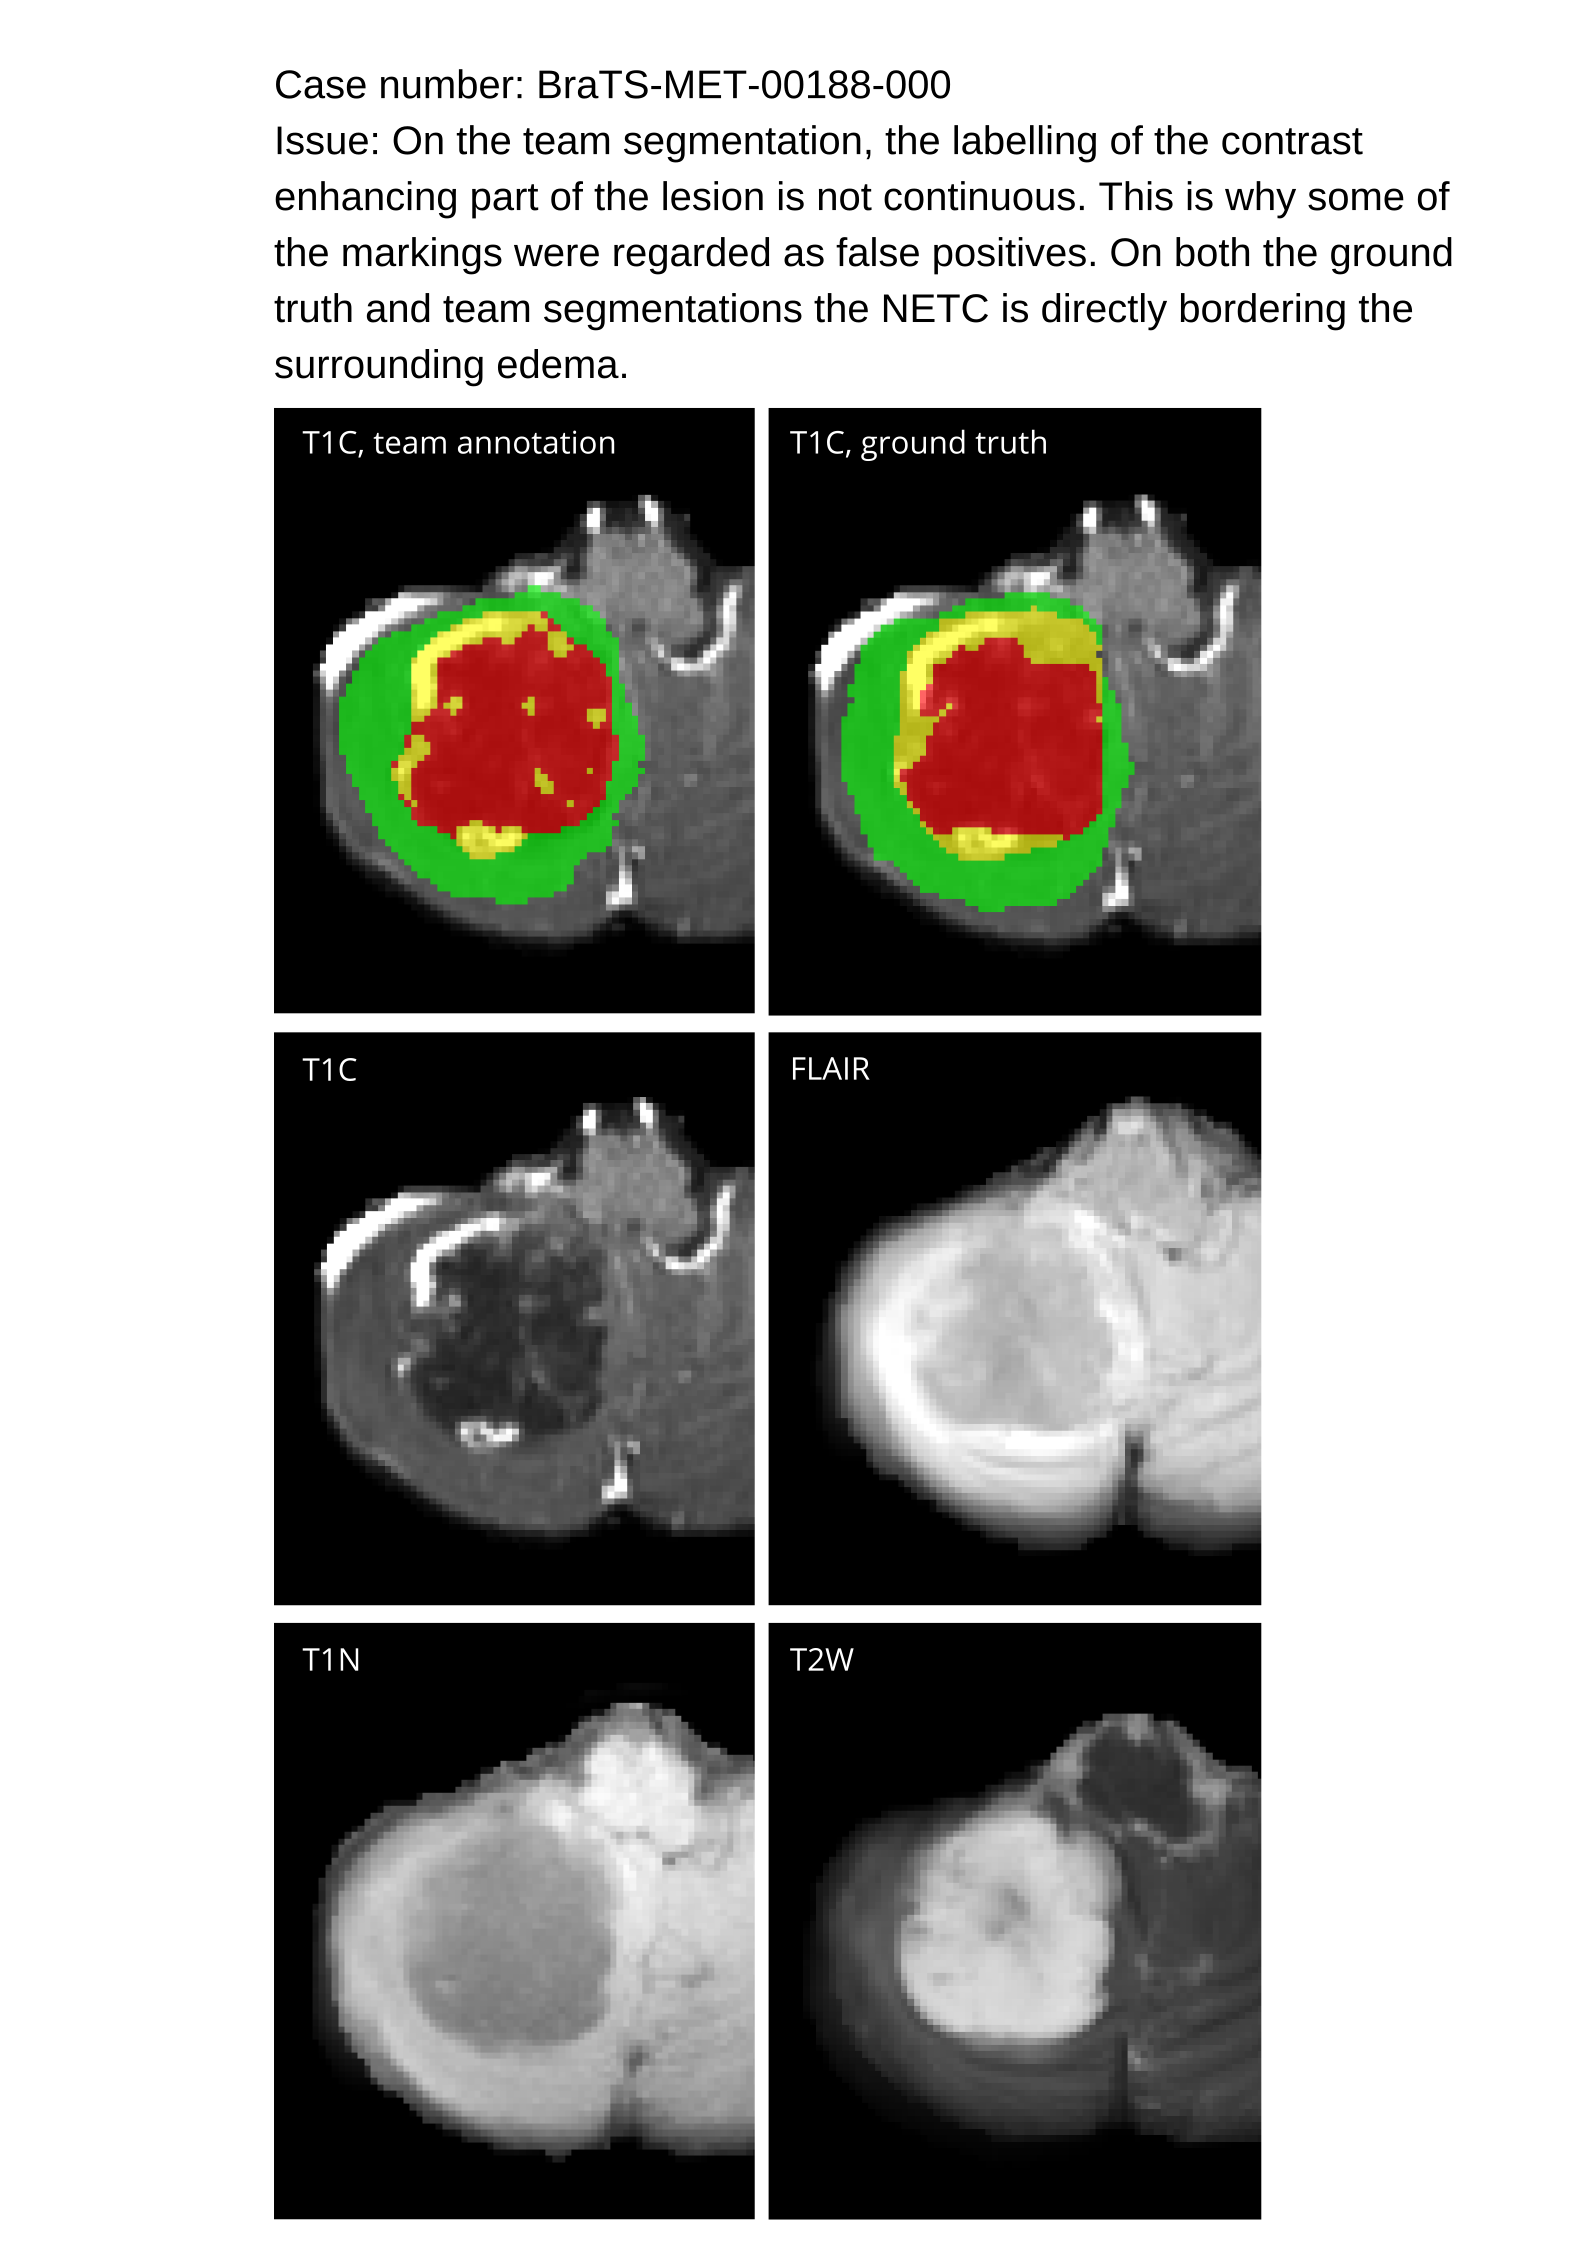

Approvers reviewed the volunteer annotations and either approved the case or returned it to students for re-annotation. Additionally, a QC process was implemented, which included removing all random voxels and any voxels outside the brain mask, ensuring all images had the same parameters (space, orientation, and origin) as the SRI24 atlas, and verifying the presence of all segmentations and segmentation masks are in the folder with original NIfTI images.